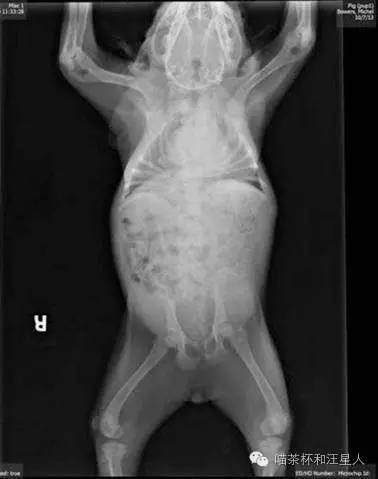

它的脊柱不完整,

甚至有一部分融合扭曲在一起。

脊椎在脖子上一分为二。

Pig的心酸X光片。